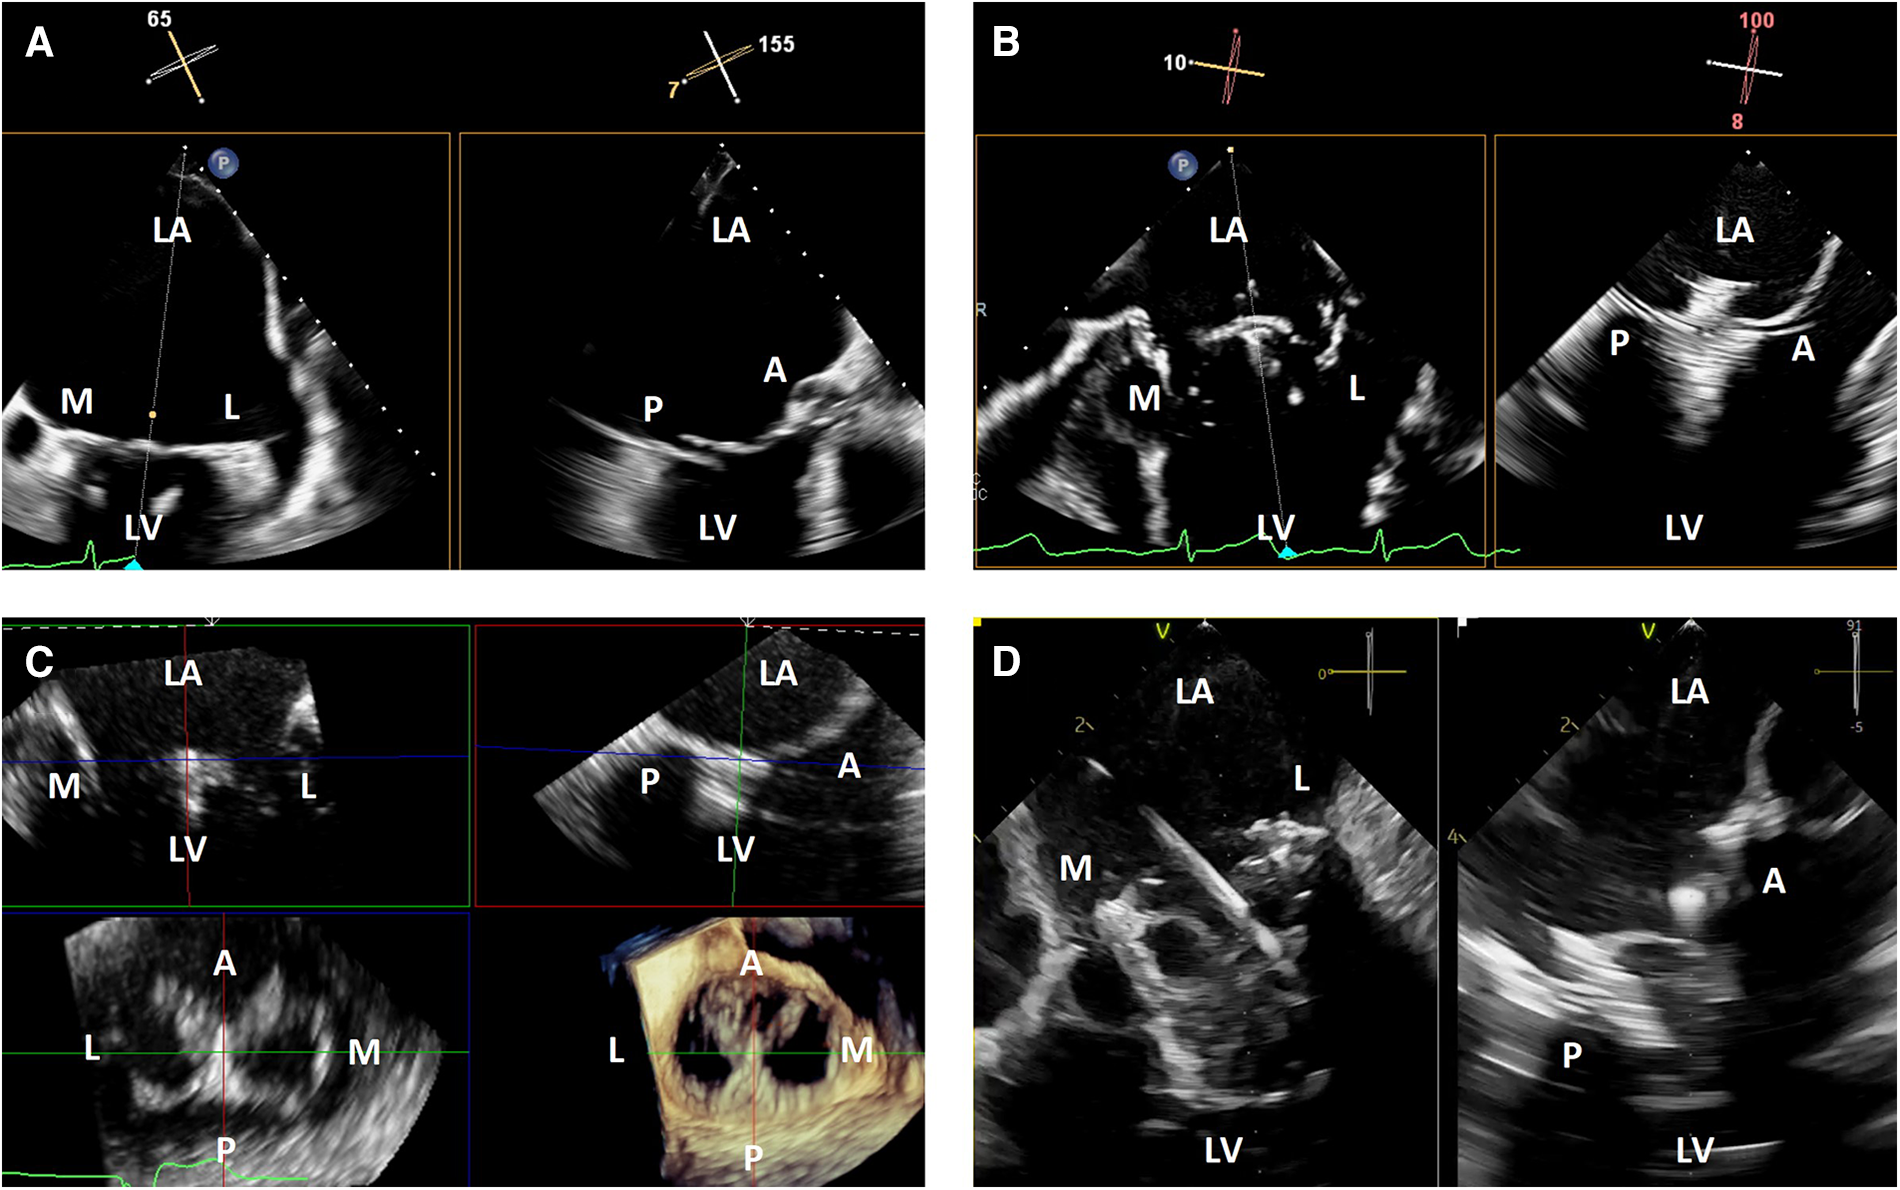

TEE imaging is excellent for transcatheter mitral interventions due to the position of the esophagus relative to the left atrium. The mitral valve is typically less than 10 cm from the probe, and when imaged from the left atrial wall opposite from the mitral valve, is well-positioned for flexible imaging of the entire valve using single plane, biplane or 3-dimensional imaging. When the left atrium is massively enlarged, the esophagus is significantly displaced laterally, or when other anatomic abnormalities limit TEE image quality, ICE may provide better intraprocedural imaging (Figure 1).

Figure 1

3-dimensional intracardiac echocardiography for transcatheter mitral interventions. (A) Biplane transesophageal echocardiography in a severely dilated left atrium causing reduced spatial resolution of the mitral valve due to its far field position; (B) biplane intracardiac echocardiography in the same patient with improved visualization of the mitral valve, allowing for a successful mitral transcatheter edge-to-edge repair; (C) live 3-dimensional multi-planar reconstruction from an intracardiac echocardiography volume after deployment of a mitral transcatheter edge-to-edge repair device; (D) biplane intracardiac echocardiography during a transcatheter mitral valve-in-valve implantation. LA, left atrium; M, medial; L, lateral; LV, left ventricle; A, anterior; P, posterior.

Angulation of the asymmetric imaging array relative to the mitral coaptation line is also affected by left or right flexion. To maximize biplane quality for leaflet segment coaptation pair visualization, such as for leaflet grasping in transcatheter edge-to-edge repair, it is best to obtain an intercommissural view at either −45 or +45 degrees so the orthogonal “grasp” or long axis view is taken at +45 or +135 degrees. As described above, this is to overcome the image degradation that occurs perpendicular to the long axis of the ICE probe (at 90 degrees) due to the crystal arrangement of the ICE matrix array. After optimization, good quality biplane, live 3-dimensional and live 3-dimensional multi-planar reconstruction can be performed similarly to TEE imaging (Figure 1).